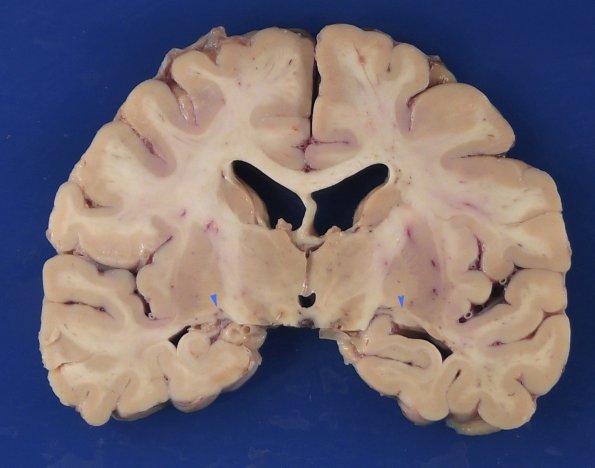

Case 5 History ---- The patient was a 64-year-old woman with a history of Wolfram syndrome (including cognitive delay, optic atrophy, and neurogenic bladder), diabetes, obstructive sleep apnea, recent pulmonary embolism and sepsis secondary to urinary tract infection. She presented to an outside hospital with shortness of breath. In the ED her vital signs were significant for hypoxia (87%) saturation and tachycardia and she was admitted for acute hypoxic hypercapneic respiratory failure secondary to multifocal pneumonia and for acute kidney injury, obstructive sleep apnea, leukocytosis and recurrent pulmonary embolism. She was transitioned to comfort care and passed away. ---- At autopsy the weight of the fixed brain was 970 g. Both optic nerves appeared atrophic and discolored. Coronal sections of the cerebral hemispheres revealed small bilateral lateral geniculate nuclei (arrowheads).